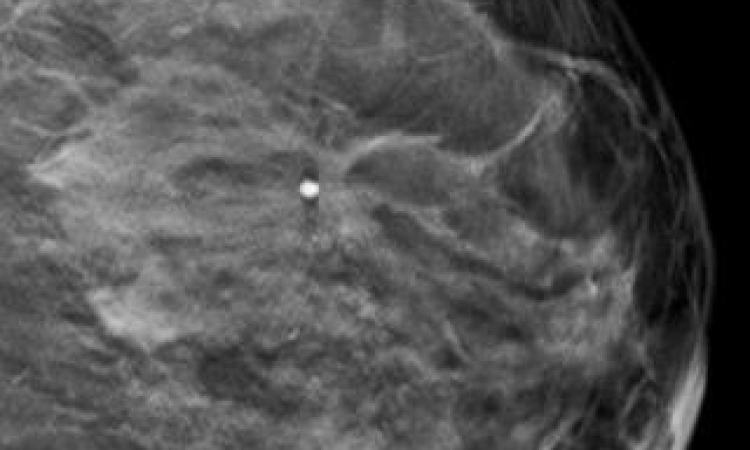

Auch in der Brustdiagnostik sind die anfallenden Datenmengen in den letzten Jahren immer komplexer geworden: multiparametrische Magnetresonanztomografie (MRT) inklusive Diffusionsbildgebung und MR-Spektrographie, Positronen-Emissions-Tomographie (PET), Tomosynthese (3D-Mammographie) und die diversen Ultraschalltechniken liefern unzählige Daten, deren Auswertung mehr und mehr zur Herkulesaufgabe werden. „Für den einzelnen Radiologen wird es immer schwieriger, all diese Informationen zu sichten, Redundantes auszusortieren und schließlich zu einer Diagnose zu kommen“, erläutert Assoc. Prof. Priv.-Doz. Dr. Pascal Baltzer von der Universitätsklinik für Radiologie und Nuklearmedizin der Medizinischen Universität in Wien, der am Freitag auf dem 96. Deutschen Röntgenkongress einen Vortrag mit dem Titel „Big Data in der Mammadiagnostik“ hält.

Die multiparametrische MRT zum Beispiel – Baltzers Forschungsgebiet – liefert eine Vielzahl von Ergebnissen. Allein auf Basis einer Durchblutungsmessung anhand von durch injizierte Kontrastmittel hervorgerufenen Signaländerungen können mittels pharmakokinetischer Modelle verschiedene Verteilungsvolumina und Durchblutungsparameter berechnet werden (z.B. Durchblutungsstärke des Gewebes, extrazelluläres Verteilungsvolumen). „Wenn man dann die anderen Techniken dazunimmt, die alle unterschiedlichen funktionelle Aspekte des Tumors darstellen – sei es die Biochemie, sei es die Mikroanatomie, sei es die Durchblutung –, dann erhält man ein recht vollständiges doch sehr komplexes Bild des Tumors“, erklärt Baltzer. Dies aber werfe eine ganze Reihe von Fragen auf: Was bedeutet der gemessene Parameter im Einzelfall? Wie sollen die einzelnen Parameter kombiniert werden? Lässt sich aus einem Wert, der sich in einer Studie als sinnvoll erwiesen hat, auch unter klinischen Bedingungen an anderen Geräten eine brauchbare Information herauslesen?